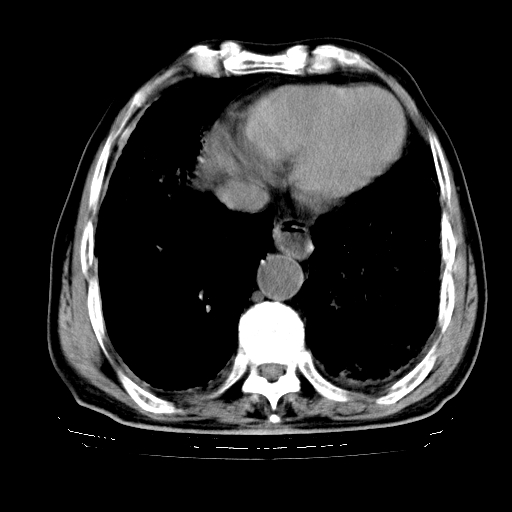

标题: CT25149:男,69岁,反复咳嗽、咳痰五年余,呼吸困难三天。 [打印本页]

男,69岁,反复咳嗽、咳痰五年余,呼吸困难三天。

慢支伴感染、肺气肿、肺心病

慢支伴感染、肺气肿、肺心病!支持!另:间质纤维化!

慢支伴感染、肺气肿、肺心病。双肺间质性改变(间质纤维化)。